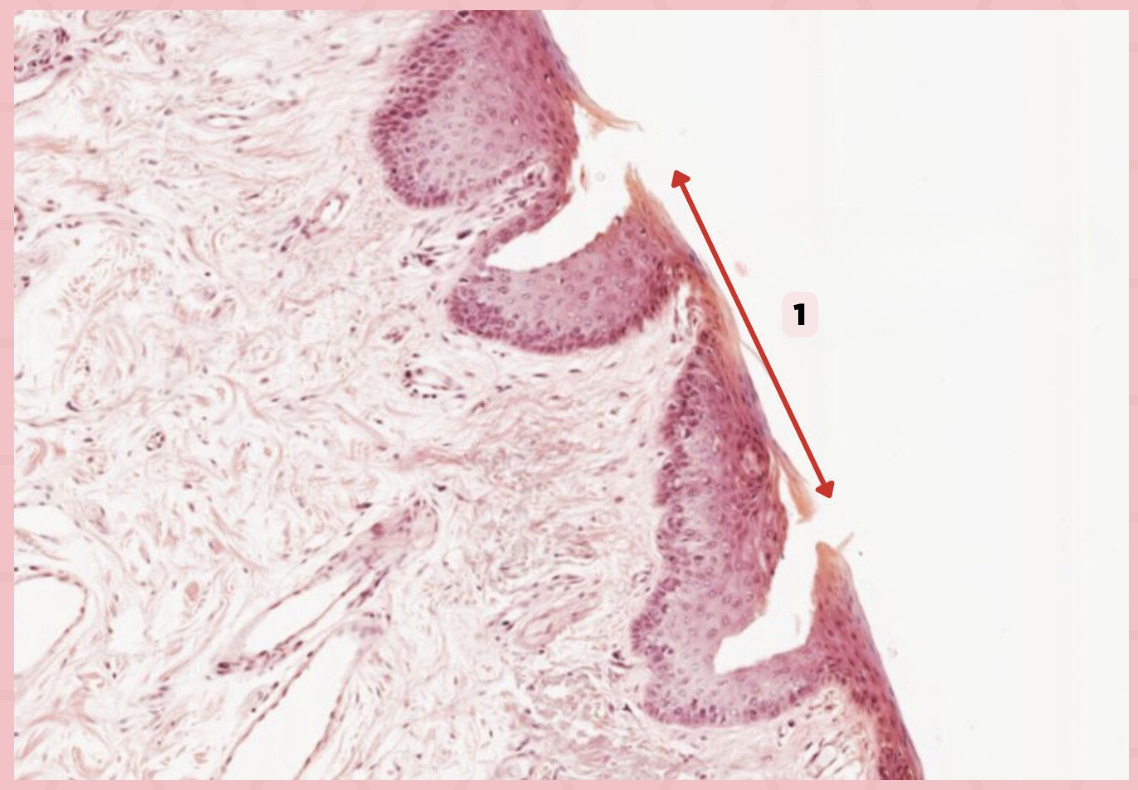

Identify the structure labelled in the given image?

a. Epidermis

b. Dermis

c. Hypodermis

d. Mucosa/Mucous Membrane

a. Keratinized stratified squamous epithelium

Identify the structure’s lining epithelium given in the image?

a. Keratinized stratified squamous epithelium

b. Nonkeratinized stratified squamous epithelium

Lip

What specimen is being showed in this picture?

Keratinized Stratified Squamous Epithelium (Epidermis)

Identify the structure labeled as 1.